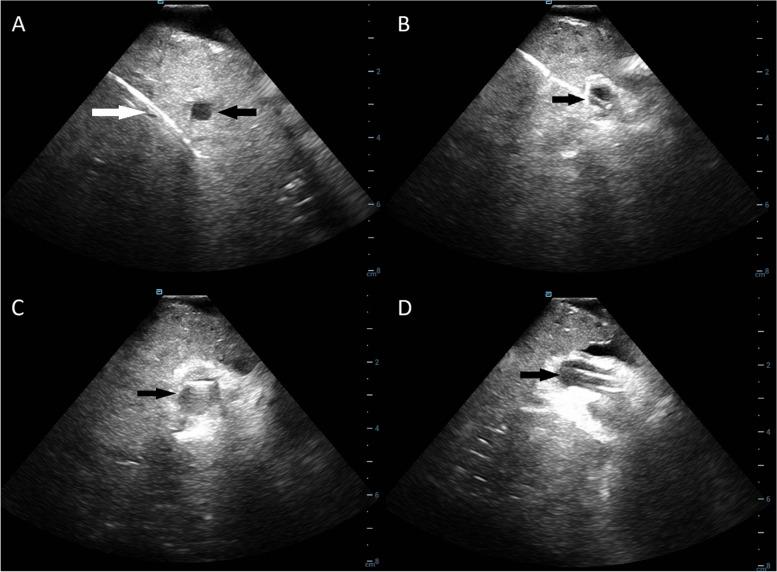

Transjugular intrahepatic portosystemic shunt (TIPS) creation remains as one of the more technically challenging endovascular procedures. Portal vein access from the hepatic vein often requires multiple needle passes, which increases procedure times, risk of complications, and radiation exposure. With its bi-directional maneuverability, the Scorpion X access kit may be a promising tool for easier portal vein access. However, the clinical safety and feasibility of this access kit has yet to be determined.

MATERIALS AND METHODS

In this retrospective study, 17 patients (12 male, average age 56.6 ± 9.01) underwent TIPS procedure using Scorpion X portal vein access kits. The primary endpoint was time taken to access the portal vein from the hepatic vein. The most common indications for TIPS were refractory ascites (47.1%) and esophageal varices (17.6%). Radiation exposure, total number of needle passes, and intraoperative complications were recorded. Average MELD Score was 12.6 ± 3.39 (range: 8-20).

RESULTS

Portal vein cannulation was successfully achieved in 100% of patients during intracardiac echocardiography-assisted TIPS creation. Total fluoroscopy time was 39.31 ± 17.97 min; average radiation dose was 1036.76 ± 644.15 mGy, while average contrast dose was 120.59 ± 56.87 mL. The average number of passes from the hepatic vein to the portal vein was 2 (range: 1-6). Average time to access the portal vein once the TIPS cannula was positioned in the hepatic vein was 30.65 ± 18.64 min. There were no intraoperative complications.

CONCLUSIONS

Clinical utilization of the Scorpion X bi-directional portal vein access kit is both safe and feasible. Utilizing this bi-directional access kit resulted in successful portal vein access with minimal intraoperative complications.

经颈静脉肝内门体分流术(TIPS)仍是技术要求较高的血管内介入手术之一。从肝静脉进入门静脉通常需要多次穿刺,这会增加手术时间、并发症风险和辐射暴露。凭借其双向可操作性,Scorpion X穿刺套件可能是一种有助于更轻松进入门静脉的有前景的工具。然而,该穿刺套件的临床安全性和可行性尚未确定。

材料与方法

在这项回顾性研究中,17例患者(12例男性,平均年龄56.6±9.01岁)使用Scorpion X门静脉穿刺套件进行了TIPS手术。主要终点是从肝静脉进入门静脉所需的时间。TIPS最常见的适应证是顽固性腹水(47.1%)和食管静脉曲张(17.6%)。记录辐射暴露、穿刺总次数和术中并发症。平均终末期肝病模型(MELD)评分是12.6±3.39(范围:8 - 20)。

结果

在心脏超声心动图辅助下进行TIPS手术时,100%的患者成功实现门静脉插管。透视总时间为39.31±17.97分钟;平均辐射剂量为1036.76±644.15毫戈瑞,而平均造影剂剂量为120.59±56.87毫升。从肝静脉到门静脉的平均穿刺次数为2次(范围:1 - 6次)。一旦TIPS套管置于肝静脉,进入门静脉的平均时间为30.65±18.64分钟。无术中并发症。

结论

Scorpion X双向门静脉穿刺套件的临床应用安全可行。使用这种双向穿刺套件可成功进入门静脉,且术中并发症最少。